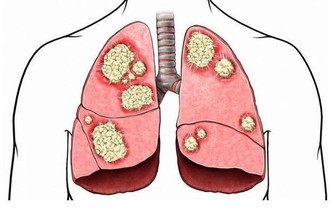

腳部出現青筋,說明血液循環不暢通,但是前期人體並不會出現其他不適應的癥狀。沒有出現不適,不代表完全沒問題。血液循環不暢通,將會導致心臟部位無法及時接受身體回流的血液,繼而影響下一輪供血;還會導致腳部功能退化,出現足部組織壞死的現象。

其實這是非常錯誤的看法,靜脈曲張本身可能是其他病變的繼發表現,如靜脈閉塞。靜脈閉塞對身體的傷害可謂是致命性的,其對心臟的傷害可想而知